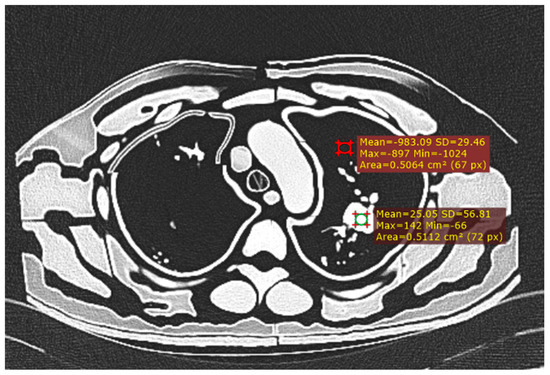

2.6. Quantitative Assessment of Image Quality

3.1. Radiation Equivalence